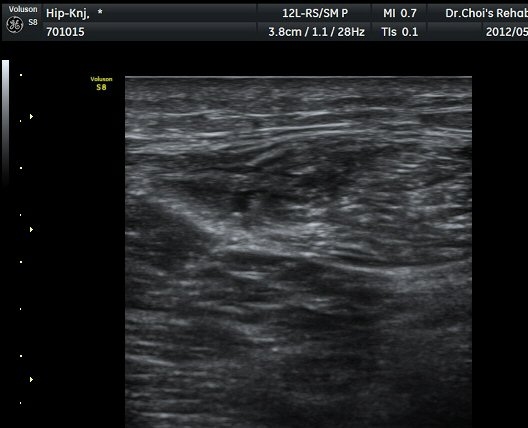

´ëÅðÁ÷±Ù Á¾´Ü¸é°Ë»ç¿¡¼­ ±ÙÀ°³»¿¡ ¼±»óÀÇ Àú¿¡ÄÚ °¢±ØÀÌ °üÂûµÈ´Ù(±×¸² 4, 5).